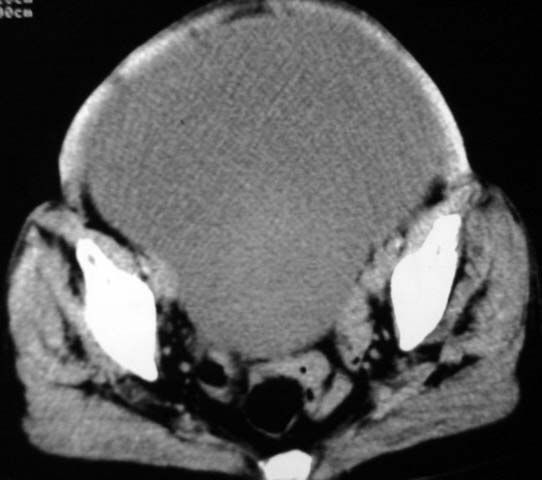

女,75岁,腹部胀大半年余,无其他症状。

考虑来源与卵巢的巨大囊腺瘤或囊肿。

真是腹大如牛,考虑卵巢巨大囊腺瘤或囊肿。

考虑来源卵巢巨大黏液性囊腺瘤。